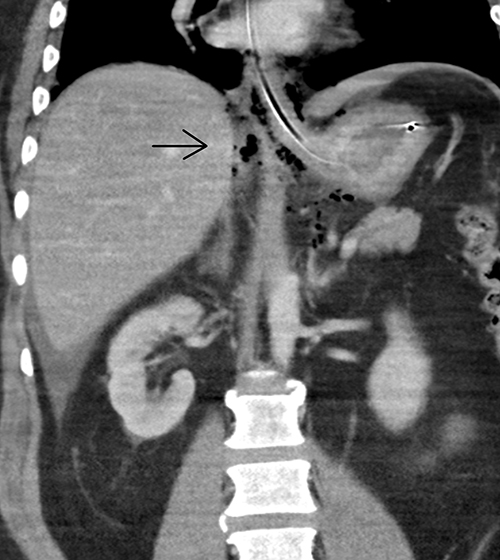

Ventrikel- eller tarmperforation, strangulation­s­ileus eller pankreatit var de differentialdiagnoser som låg närmast till hands. Omedelbar laparotomi övervägdes, men då tillståndet stabiliserades något valde vi, efter diskussion med inringd radiolog, att först utföra datortomografi av buken. Omedelbar tolkning av radiolog gav direkt muntligt besked om smärre mängder fri gas samt spridd gas retroperitonealt bakom pankreas och intill mesenterialroten (Figur 1). I första hand förelåg misstanke om perforerat ulcus duodeni, men bilden bedömdes även kunna stämma med en perforation i gastroesofageala övergången.

Figur 1. Måttliga mängder fri gas högt i buken.